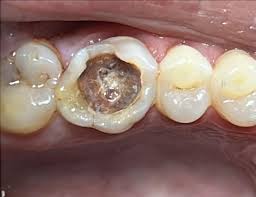

Gros plan d'une molaire avec une carie profonde visible nécessitant un plombage dans le cabinet de nkoldongo

Dent percée ou cariée

Traitement d'une carie : 15 000 – 40 000 FCFA